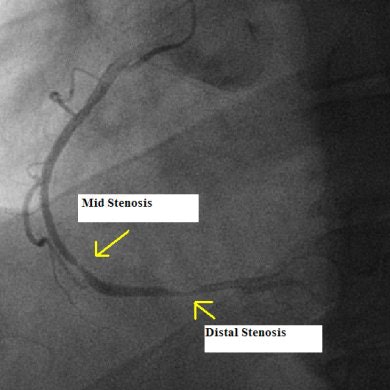

![]() |

| Cardiac cath image demonstrates correlation with CTA. Image courtesy of Dr. Benjamin Roach. |

The interventional procedure confirmed the CT findings: there was minor plaque buildup in my left artery, but not enough to warrant a stent. Then the cardiologist began imaging my right artery. I saw him pass the areas of interest once, then double back to look again. Again the CT findings were confirmed. I had two significant blockages of almost 90%. Ten minutes later they were both stented and wide open. Three days later I was back to 100% and watching my son's football game.